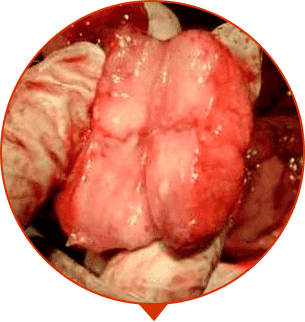

• АДЕНОМИ ПРОСТАТИ

Розростання тканин передміхурової залози, утворення пухлин і "ганглії".

• ОНКОЛОГІЯ

Злоякісна пухлина, найчастіша причина смерті чоловіків

ЕФЕКТИВНІСТЬ КЛІНІЧНО ДОВЕДЕНО

Клінічні випробування проводилися в санаторії на базі лікарні у Харкові в 2013 році. У клінічних дослідженнях брали участь чоловіки віком від 38 до 73 років з діагнозом хронічний простатит на 1 місяць.